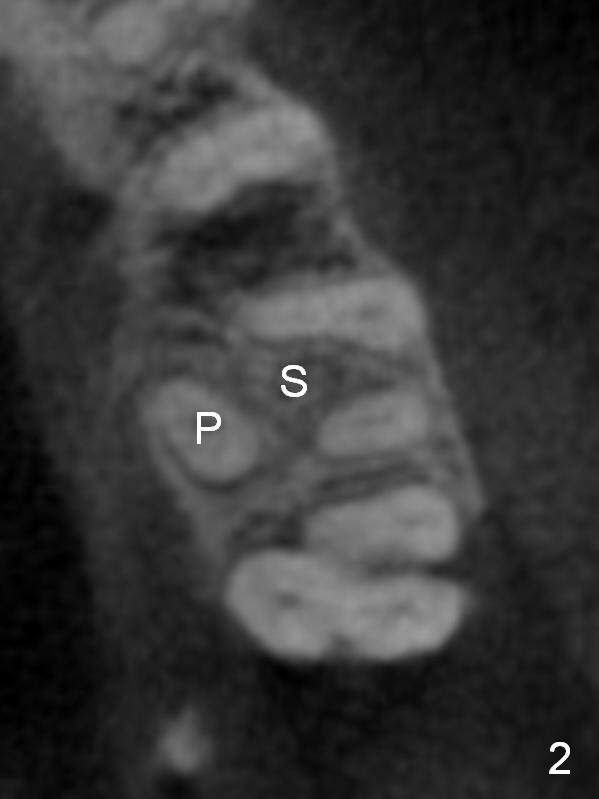

It is noteworthy that the tooth #14 was less affected than #15 22 months earlier (Fig.1 (CBCT sagittal section), 2 (axial), 3 (coronal)). Calculus on the surface of the palatal root (Fig.6 P) is associated with the palatal abscess (Fig.5 P). S: septum.